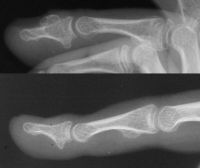

Distal phalanx osteochondroma. This painless unusual benign tumor resulted in a severe nail plate concavity.